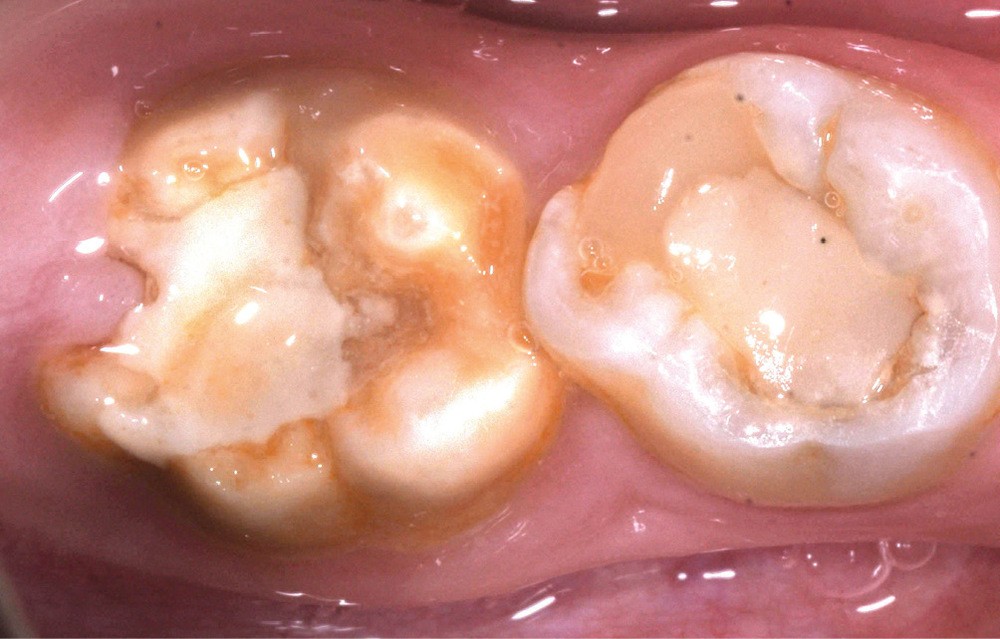

Une patiente de 10 ans se présente en consultation. Aucun antécédent médical ou chirurgical n’est constaté. À l’examen clinique, nous observons une forme sévère de MIH sur 36 et 46 avec des fractures post-éruptives [1] (fig. 1a et b). En raison de cette pathologie, la patiente se plaint de sensibilités spontanées sur ces dents, ayant un impact sur sa qualité de vie, et une maîtrise difficile de l’hygiène bucco-dentaire. Les secteurs antérieurs maxillaires et mandibulaires présentent aussi des opacités délimitées entraînant une gêne esthétique conséquente pour la patiente.